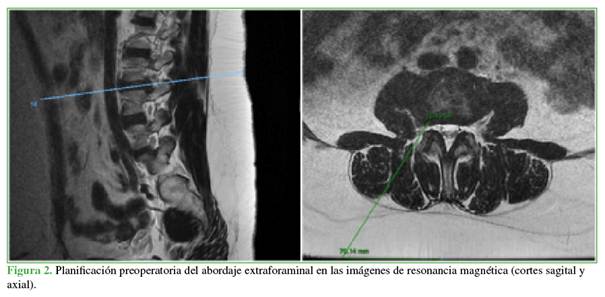

Discectomía endoscópica extraforaminal

Bajo anestesia general, se coloca al paciente en decúbito prono. A diferencia de la técnica transforaminal, se realiza un abordaje posterolateral que se planifica con los estudios preoperatorios (Figura 2), ya que, para hernias extraforaminales, no es necesario un abordaje tan lateral. Es una técnica dificultosa para hernias de L5-S1 en donde las crestas ilíacas molestan en la vía de acceso, por lo que es un procedimiento ideal para los niveles L4-L5 hacia arriba.

Se realiza un control radioscópico anteroposterior estricto, buscando observar las plataformas paralelas al disco por tratar. Se marca la línea media y luego hacia lateral según la planificación. Se procede a colocar el dilatador y luego se introduce el endoscopio. Mediante un control radioscópico se verifica la correcta posición. Habitualmente, si la planificación ha sido correcta, lo primero que se observa es la hernia extraforaminal (Figura 3).